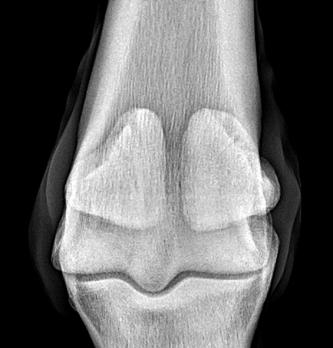

REDUCING THE RISK OF FRACTURES

Preventing serious fractures in the racehorse

Christopher Riggs tells us of the work being done on the prevention of serious fractures in the racehorse.